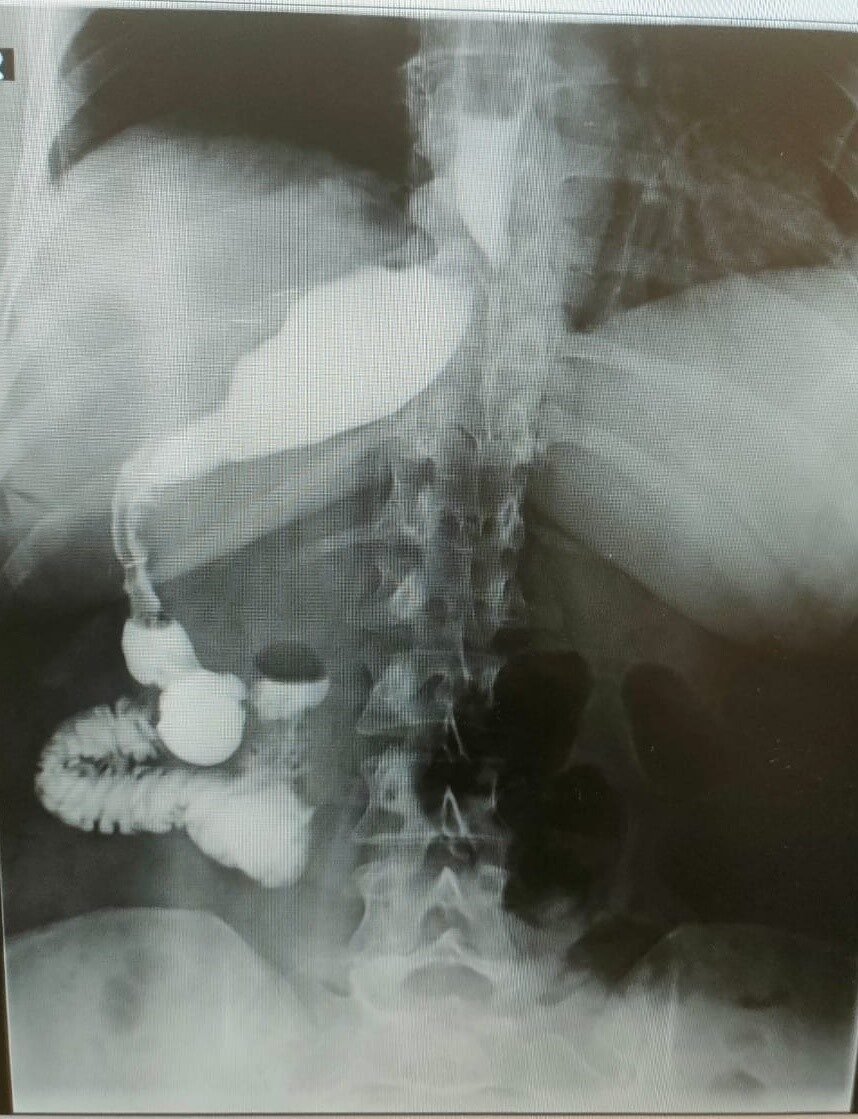

Ameliyatı gerçekleştiren Memorial Antalya Hastanesi Genel Cerrahi Bölüm Başkanı Prof. Dr. Alihan Gürkan, yaşadıkları şaşkınlığı şu sözlerle dile getirdi: “Çok yapılan bu operasyonlar içerisinde hastanın değişik bir anomalisi vardı. 100 binde bir görüldüğü söyleniyor. Organların hepsi ters olabiliyor. Bu daha sık görülen bir şey ama bu hastada bütün organlar yerli yerinde ama sadece mide sağ tarafa kaymış. Yani karaciğerin arkasına gitmiş. Operasyona başladığımızda mideyi bulamadık. Karaciğeri kaldırınca mideyi sağ tarafta gördük. Bu çok nadir bir durum. 2023 yılı verilerine göre, böyle bir tüp mide ameliyatı dünyada yalnızca 50 kişiye uygulanmış. Biz de bu vakayı başarıyla gerçekleştirdik. Teknik açıdan bizi zorlayan ancak deneyimimizi artıran bir ameliyat oldu”.

Prof. Dr. Gürkan, ameliyatın detaylarına değinerek, “Tüp mide operasyonunun ayna görüntüsünü yaptık. Normalde sol tarafta yaptığımız obezite ameliyatını bu hastada sağ tarafta gerçekleştirdik. Midenin karaciğerin arkasında olması ameliyat süresini 15 dakika uzattı ve toplamda 1 saat sürdü. Bizim için de hoş bir tesadüf oldu” diye konuştu.